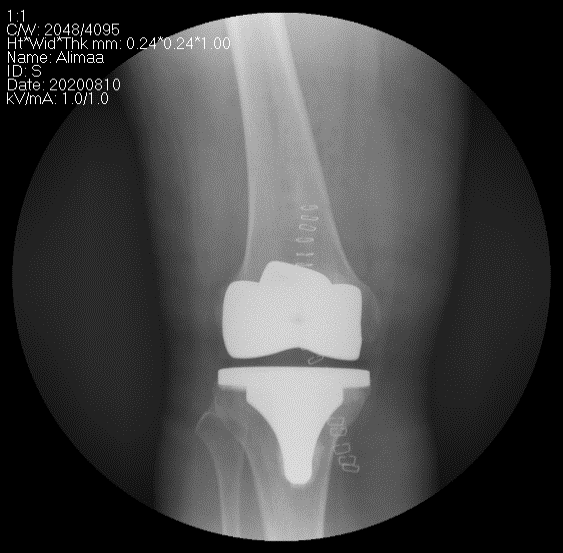

Өвдөгний үе бүтэн солих мэс засал (TKA) image2

Эгц урдаас

Хажуугаас

Рентген, эгц урдаас харуулсан байдал

Өвдөгний үе бүтэн солих мэс засал (TKA) image10

Рентген, хажуугаас харуулсан байдал